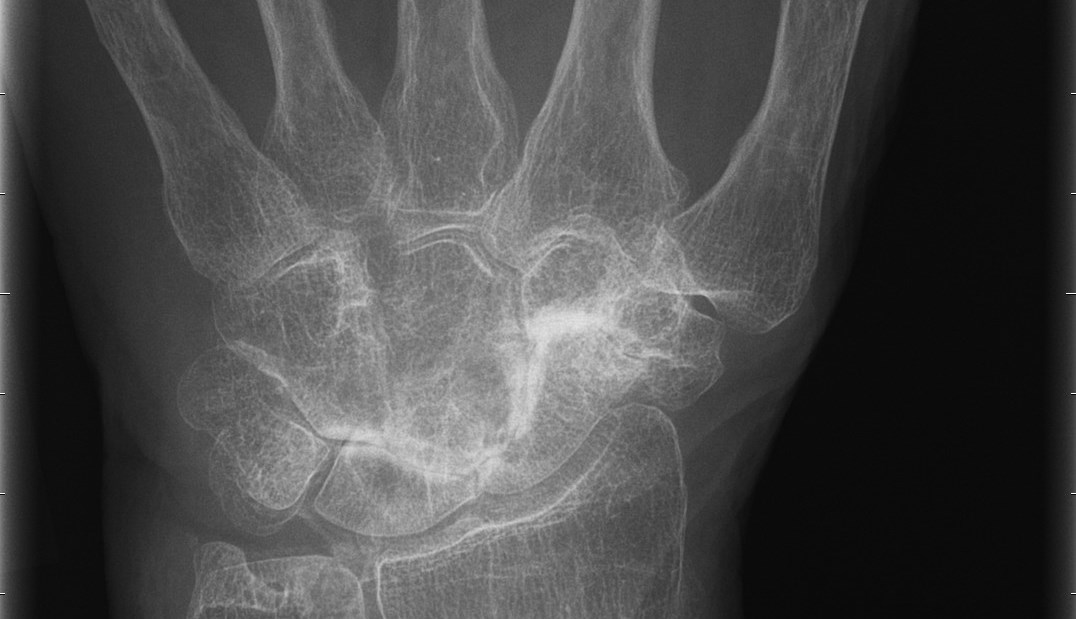

Den vanligaste lokalisationen av primär artros i handen är i tummens carpometacarpalled (CMC 1) – tumbasartros, med eller utan samtidigt engagemang av leden mellan scaphoideum och trapezium (STT-leden).

Tillståndet är 8-10 ggr vanligare hos kvinnor och debuterar vanligen mellan 45-50 år. Kliniskt finner man krepitationer i den engagerade leden samt smärta (”Grinding-test”) vid provokation i form av axial kompression och rotation av tummens bas. Vid engagemang av STT-leden har patienten smärta i handleden vid radialdeviation. Diagnosen fastställs radiologiskt.